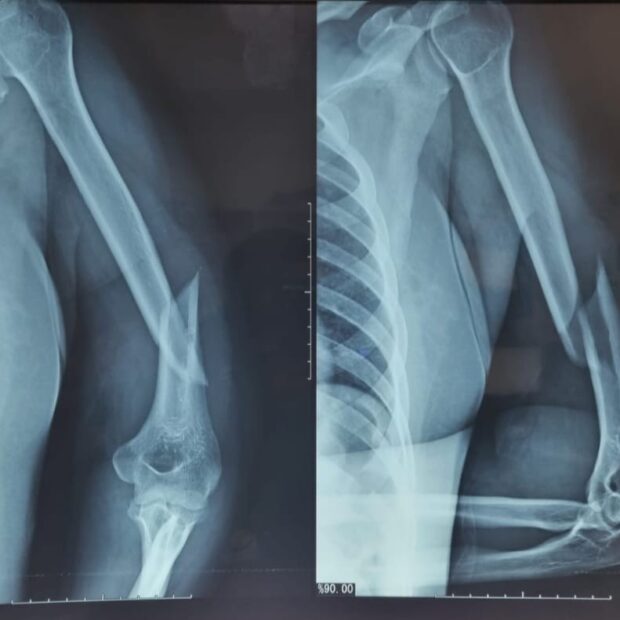

A ocorrência foi registrada por volta das 11h, quando equipes das viaturas 4593 e 3371 foram acionadas via COPOM para atender um chamado de violência doméstica na QNM 40. Ao chegarem, os policiais encontraram a mulher com hematomas no rosto, inchaço nos olhos, sangramento pelos ouvidos e o braço esquerdo fraturado. De acordo com informações do SAMU, o quadro clínico indicava trauma cranioencefálico (TCE).

A vítima relatou que vinha sendo espancada desde a meia-noite pelo companheiro. Uma vizinha, ao ouvir os pedidos de ajuda, chamou a polícia pelo 190, o que permitiu o resgate. A mulher foi levada ao Hospital Regional de Taguatinga (HRT), onde permanece internada e aguarda cirurgia de reconstrução no braço esquerdo.